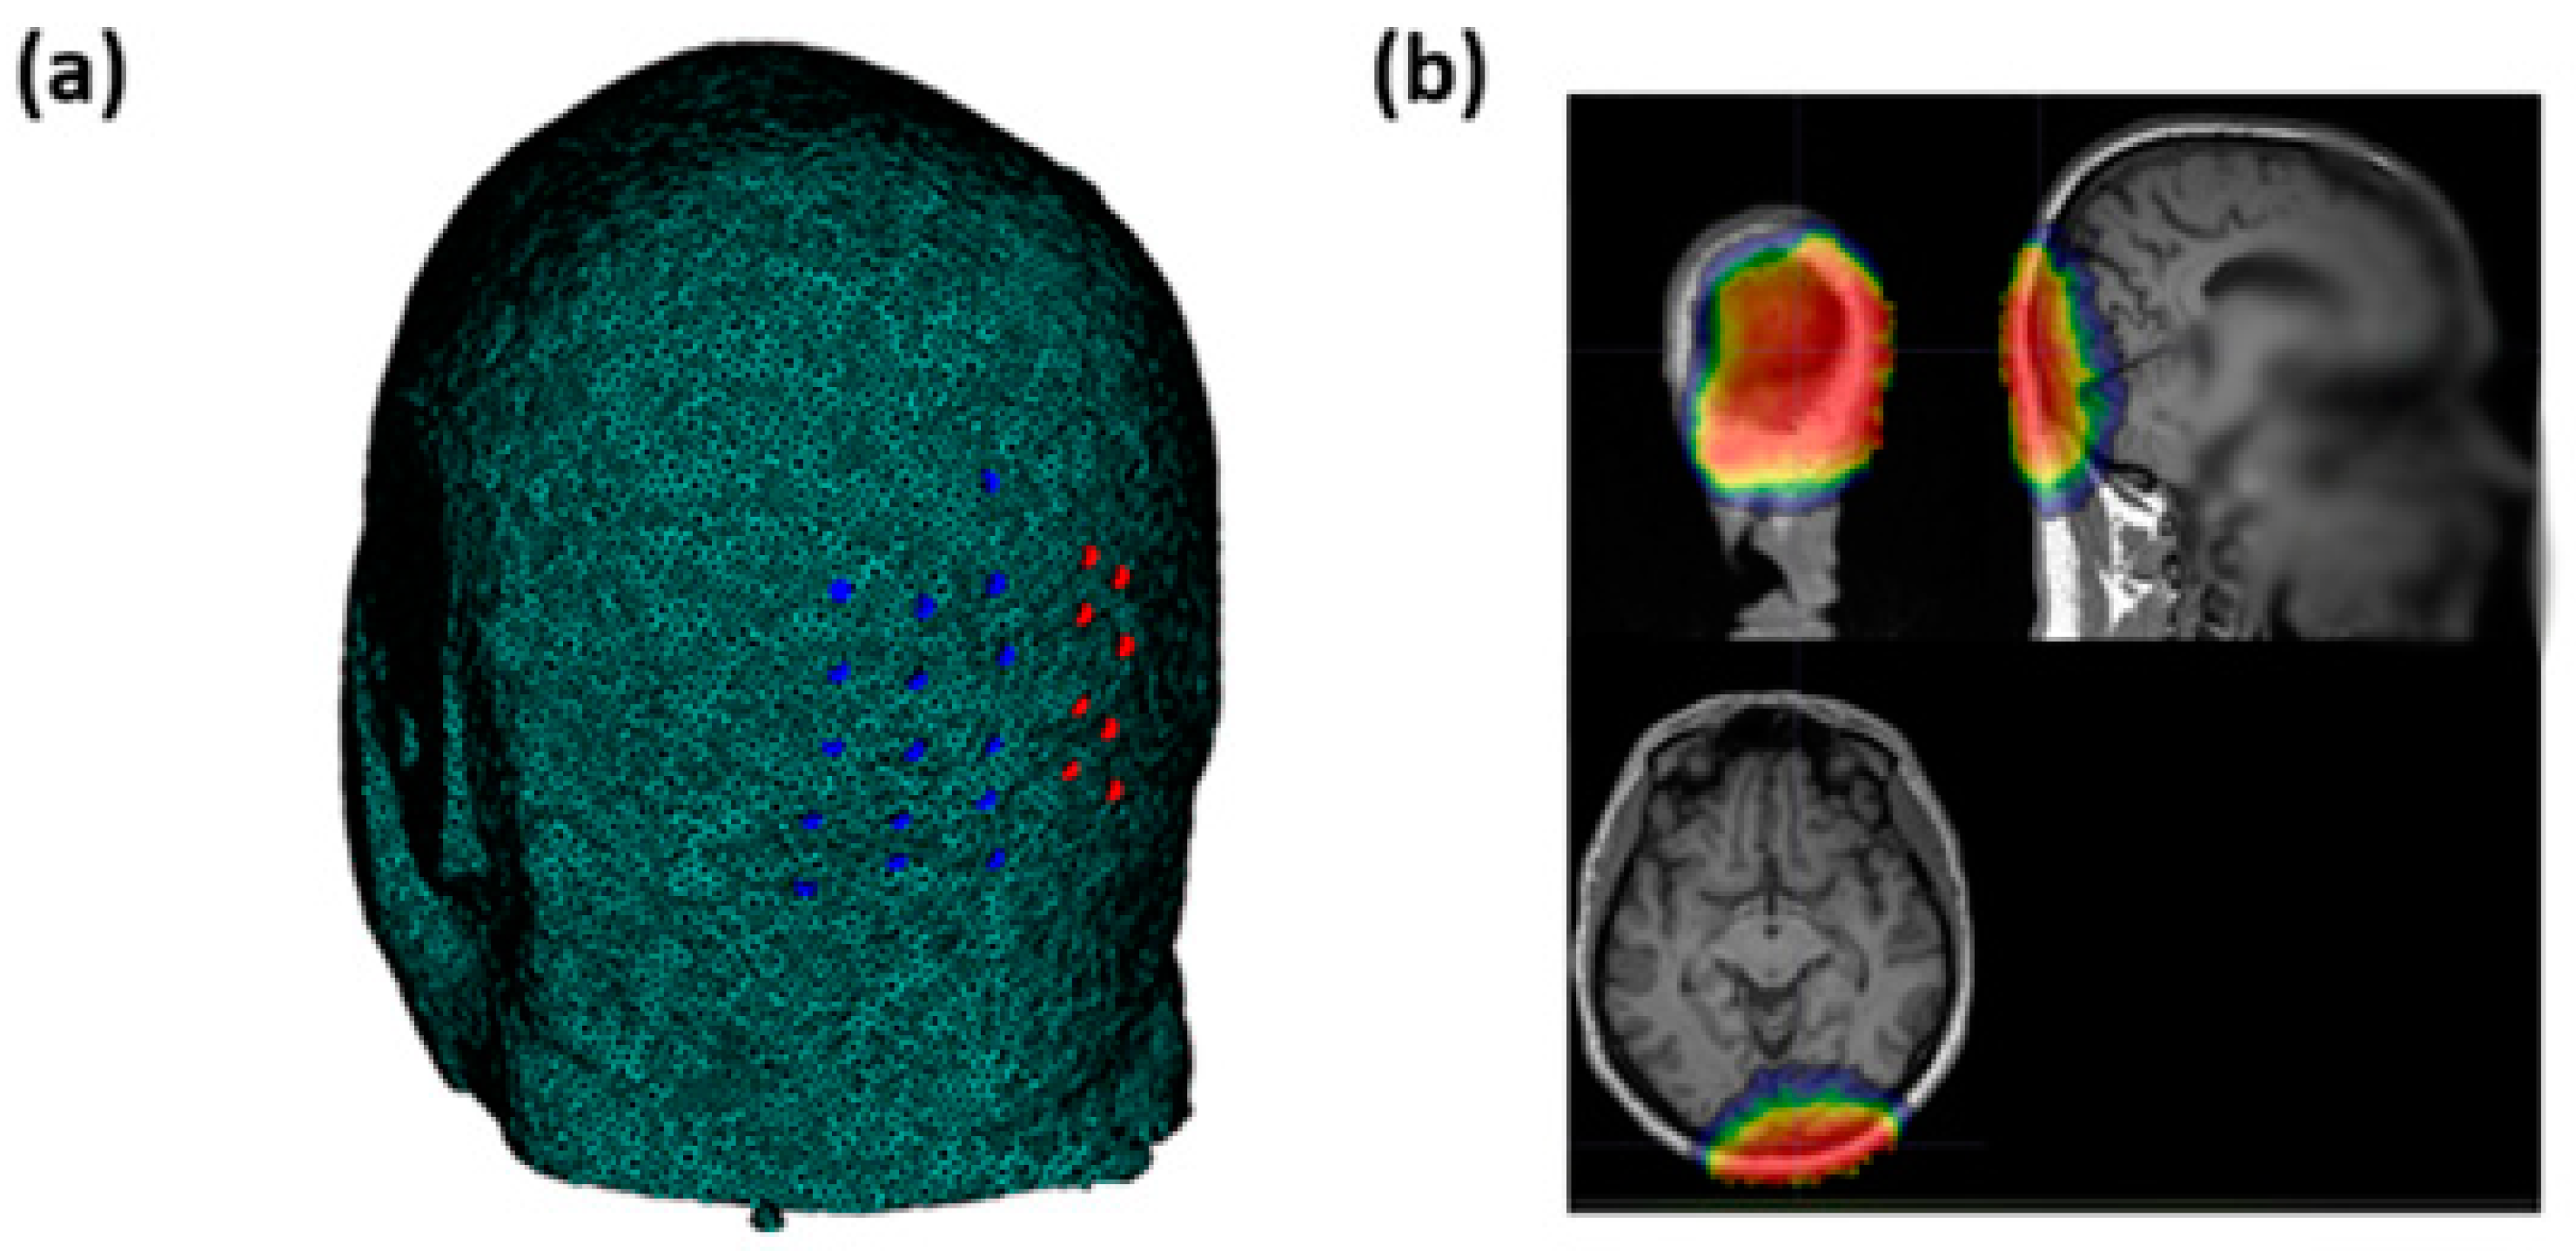

Optical signals were recorded using an integrated set of 6 frequency-domain oximeters (Imagent, ISS Inc., 1602 Newton Dr, Champaign, IL, USA). The system consisted of 32 sources (16 laser diodes emitting at 690 nm and 16 emitting at 830 nm) and 16 Photomultiplier Tube (PMT) detectors, 8 of which were used for the current study. The light emitted by the sources was time-multiplexed and modulated at 110 MHz. To generate a 6.25 kHz heterodyne detection, the current supplying the PMTs was modulated at 110.00625 MHz. In addition, a Fast Fourier Transform (FFT) was applied to the 50 kHz sampled output current of the PMTs. Transformation to frequency domain enabled the recording of the average signal intensity (Direct Current, DC), modulated signal intensity (Alternating Current, AC), and phase delay (PH). Because of multiplexing across sources, the effective sampling rate for each channel (source–detector combination) was set at 39.0625 Hz, which is suitable for FOS recording [29]. To assess FOS responses to visual stimulation, we measured optical signals from the occipital region (centered around the Oz electrode location based on the standard 10–20 EEG system) using a custom helmet consisting of 16 source fibers (each source fiber composed of two sources at 690 nm and 830 nm of wavelength) and 16 detectors (Figure 2a). The optodes were arranged to create 256 overlapping channels (128 per wavelength) at different source–detector distances ranging from 20 to 70 mm. This montage allowed for different depth sensitivities covering the visual cortex. The average sensitivity map is reported in Figure 2b in a representative subject.

Figure 2. (a) Sources’ (blue circles) and detectors’ (red circles) locations on the occipital region. (b) Average sensitivity map obtained through the optical pad employed in an exemplary subject of the study.